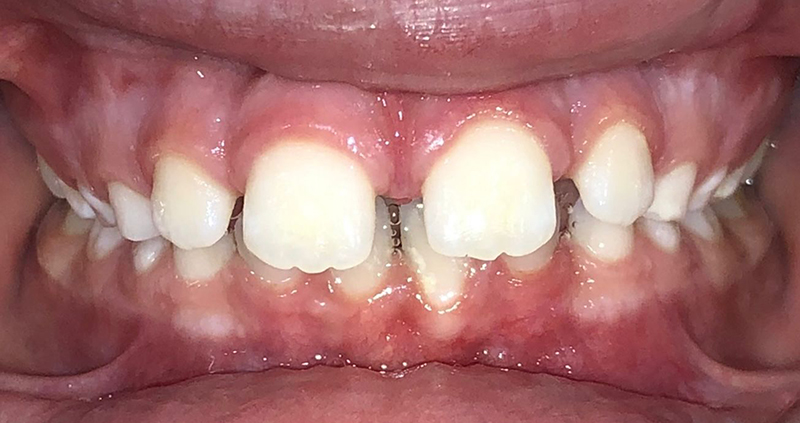

Actual Patient: Alexander

Alexander Before 4 Alexander After 4

Severe “Underbite”, Narrow Jaws, Adult Teeth Not Growing In

Alexander Before 1 Alexander After 1

Front View

Top View

Right & Left Sides